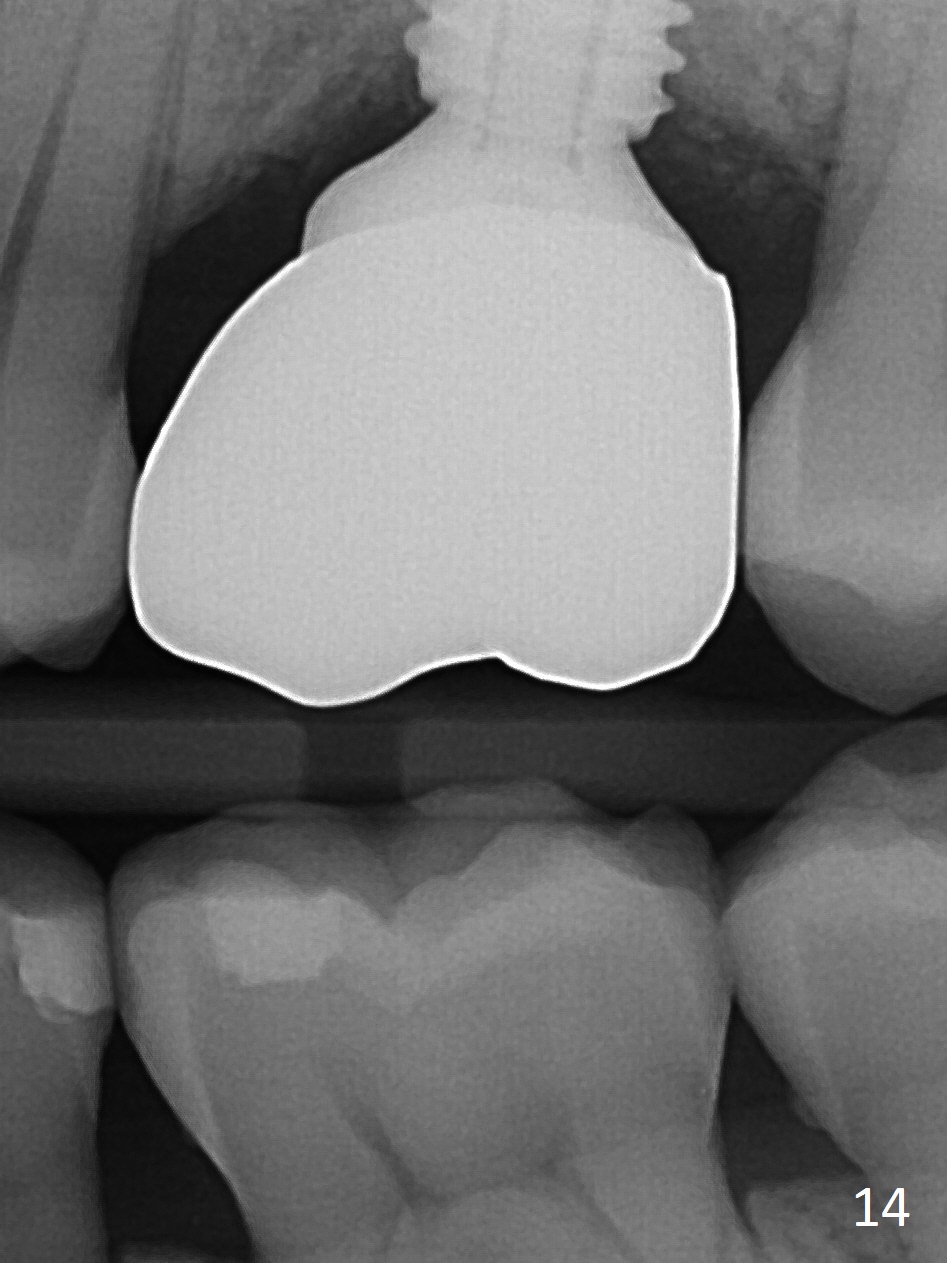

The patient experiences palatal gingival tenderness 5 months post cementation, probably due to loose proximal contacts and excessive use of floss. PA shows new normal bone next to the upper threads (Fig.12 arrow), while new less dense attached to the most coronal threads (*). BWs (Fig.13,14) shows that new bone has grown into the area between the most coronal 2 threads (arrows). When the crown and abutment are removed, the gingiva looks normal except minor laceration buccally. A 7.5x4 mm healing abutment is placed. If the infection resolves, pick up impression will be taken to add porcelain to the proximal surfaces to prevent food impaction.